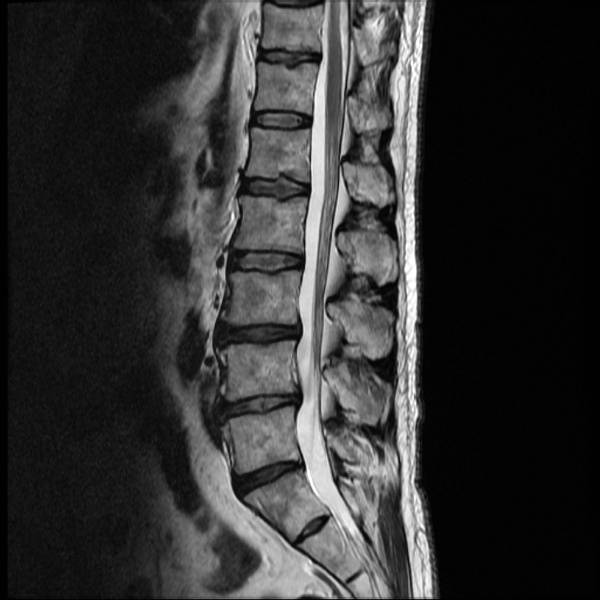

Anschließend wird eine körperliche Untersuchung durchgeführt, um die Ursache für die Schmerzen im unteren Rücken einzugrenzen. Gegebenenfalls kann ein bildgebendes Verfahren wie ein Röntgen oder eine MRT veranlasst werden.